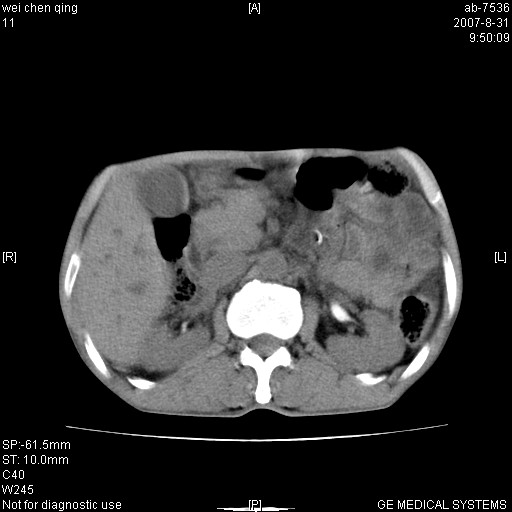

以下是引用zyyzzy在2007-8-31 14:34:00的发言:[br]该病人肝内胆管扩张,胆囊及胆总管未见明显扩张。在倒数第9层图像上可看到左右肝管结合部(肝总管)有软组织影,此处应薄层扫描。考虑肝总管占位(ca)、腹水。[br]